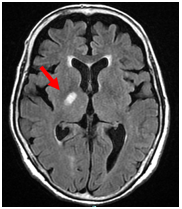

MRI;FLAIRA

【MRI;FLAIR】

MRIでは1.5cm以下の小さな梗塞として描出。